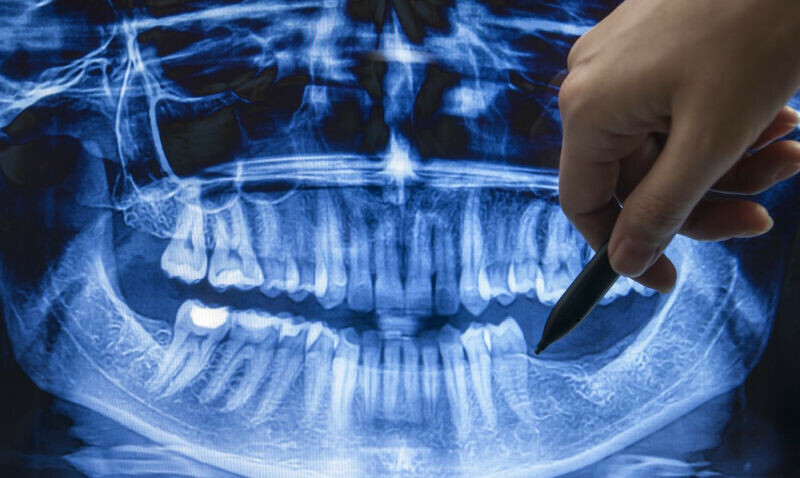

Ученые научились выращивать новые зубы

Фото: РИА Новости Японские ученые с сентября начнут исследования по выращиванию новых зубов у людей.

Фото: РИА Новости Японские ученые с сентября начнут исследования по выращиванию новых зубов у людей. Успешные практические испытания уже прошли на собаках и мышах.

Пока речь идет о пациентах с врожденной олигодонтией - отсутствием шести или более зубов.

«У пациентов с аплазией зубов в период развития челюстной кости в юном возрасте наблюдается отсутствие зубов, что делает сложным использование зубных протезов и имплантатов. В период роста наблюдается снижение функции жевания, что негативно сказывается на развитии и может привести к атрофии костей, поддерживающих зубы», - поясняют эксперты Медицинского исследовательского института при Больнице Китано в Осаке.

На помощь пришли мыши: у некоторых с генетическим дефектом белка USAG-1 формируются избыточные зубы, при этом «скрещивание мышей с аплазией зубов и мышей с избыточными зубами с дефектом гена USAG-1 приводит к восстановлению формирования зубов». Местное введение нуклеиновой кислоты USAG-1siRNA мышам с аплазией зубов позволяет восстановить отсутствующие зубы. Этот же способ испытали на собаках породы бигль, которые наравне с мышами имеют высокую степень аминокислотного сходства белка USAG-1 с человеком.

Теперь дошли руки и до человека - для этого к осени отберут «мужчин без видимых проблем со здоровьем в возрасте от 30 до 65 лет, у которых отсутствует один или более моляров». Продлятся исследования до августа 2025 года, сообщает РИА Новости.